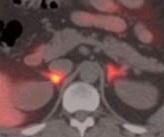

5% des cas d'hypertension artérielle durable sont dus à une petite tumeur bénigne située sur les glandes surrénales (en rouge sur visuel ci-contre) qui affecterait les niveaux d'hormones du corps. Cette maladie, nommée syndrome de Conn pourrait désormais être détectée simplement par ce test développé par des chercheurs de Cambridge. Des conclusions relayées dans l'édition du du Journal of Clinical Endocrinology & Metabolism qui si elles ne concerneront certes qu'une minorité de patients souffrant d'HTA, offre une nouvelle alternative non invasive du syndrome de Conn.

Source:The Journal of Clinical Endocrinology & Metabolism November 23, 2011Evaluation of the Sensitivity and Specificity of 11C-Metomidate Positron Emission Tomography (PET)-CT for Lateralizing Aldosterone Secretion by Conn's Adenomas. (Visuel NHS: Petite tumeur (en rouge) sur les glandes surrénales)